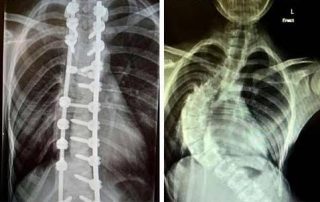

Junho verde: mês de conscientização sobre a escoliose

Dados da Organização Mundial de Saúde indicam que cerca de 6 milhões de brasileiros têm uma curvatura significativa de escoliose, que não consiste em uma doença, mas sim em uma alteração para alguns dos lados da curvatura natural da coluna vertebral. O mês de [...]